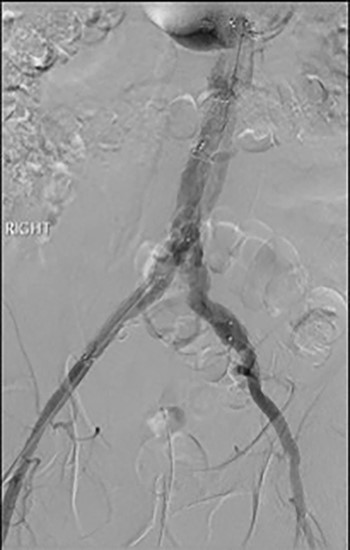

Post-EVAR angiogram showing acute thrombosis of the right limb and subtotal thrombosis of the left limb and trunk.

An angiogram at this stage demonstrated acute thrombosis of the right limb, and subtotal thrombosis of the left limb (Fig. 2). A further bolus of 2000 units Heparin was given intravenously. Thrombectomy was performed by advancing the 16Fr Sentrant sheaths into the limbs of the endograft followed by retraction under negative pressure. This manoeuvre restored antegrade arterial flow on both sides although there was a large volume of acute thrombus within the limbs of the endograft. A decision was made to perform intra-arterial thrombolysis. The 16Fr Sentrant sheath was removed from the left common femoral artery and haemostasis secured with the Proglides. The right-sided 16Fr sheath was downsized to 8 Fr sheath (the Proglide sutures were tightened around this sheath, achieving haemostasis around the smaller sheath). A multi-side hole straight angiographic catheter was placed in the body of the endograft for the thrombolysis. A bolus of 5 mg Actilyse (Boehringer Ingelheim, Ingelheim am Rhein, Germany) was given through this followed by a 1 mg/h infusion. An IV heparin infusion was started at 1000 units/h through the side arm of the 8 Fr sheath.